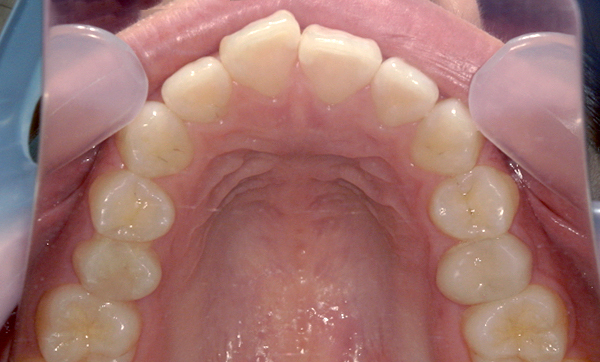

症例_007 前歯「捻転歯」症例

治療期間:10ヶ月金額:30万円+税20代女性少しのねじれ上の前歯だけ

| Before | After |